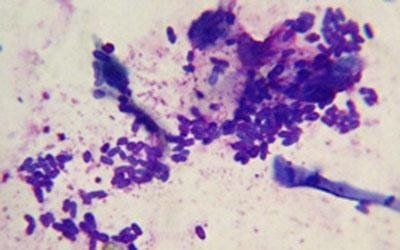

a nostra clinica esegue visite dermatologiche riguardanti direttamente o indirettamente la cute, il mantello e gli annessi cutanei del cane, del gatto e dei piccoli animali da compagnia in generale. Arrivare a una diagnosi in dermatologia vuol dire attraversare diverse tappe: accurata anamnesi remota e recente riguardante comparsa dei primi sintomi o le lesioni e loro localizzazione, eventuali trattamenti medici, presenza di prurito, tipo di alimentazione, presenza o meno dei parasiti cutanei, le allergie a contatto ecc. Viene fatto in seguito all’anamnesi un accurato esame clinico, generale e particolare del tutto l’organismo con particolare riguardo alla cute e ai suoi annessi. A tal proposito possono essere suggeriti al cliente alcuni esami particolari: uno scotch test, un esame tricoscopico, un raschiato cutaneo, il prelievo del sangue, la ricerca di dermatofiti, i test allergologici e patoistologici, prelievi bioptici ecc. Quando si raggiunge una diagnosi dermatologica di certezza, s’instaura una terapia farmacologica, la dieta a secondo del problema per raggiungere alla guarigione clinica.

Ci sono un gran numero di malattie della pelle che influenzano la salute degli animali domestici. Questi disturbi possono essere il risultato di una malattia infettiva o non infettiva, infestazione parassitaria o reazione allergica. Poiché molte di queste malattie della pelle portano stretta somiglianza sintomatica l'uno all'altro, diagnosi e trattamento adeguato spesso richiede la consultazione di un veterinario con particolare interesse in questo settore.

Diagnosticare la causa di problemi di pelle può essere come lavoro investigativo - escludere una possibilità alla volta. E 'importante utilizzare un approccio metodico per essere certi della causa principale, e cerchiamo soluzioni semplici prima di iniziare con i trattamenti spesso costosi. Vogliamo che la risoluzione e la gestione di un problema della pelle cronico di essere gratificante per l'animale domestico, il proprietario e veterinario.